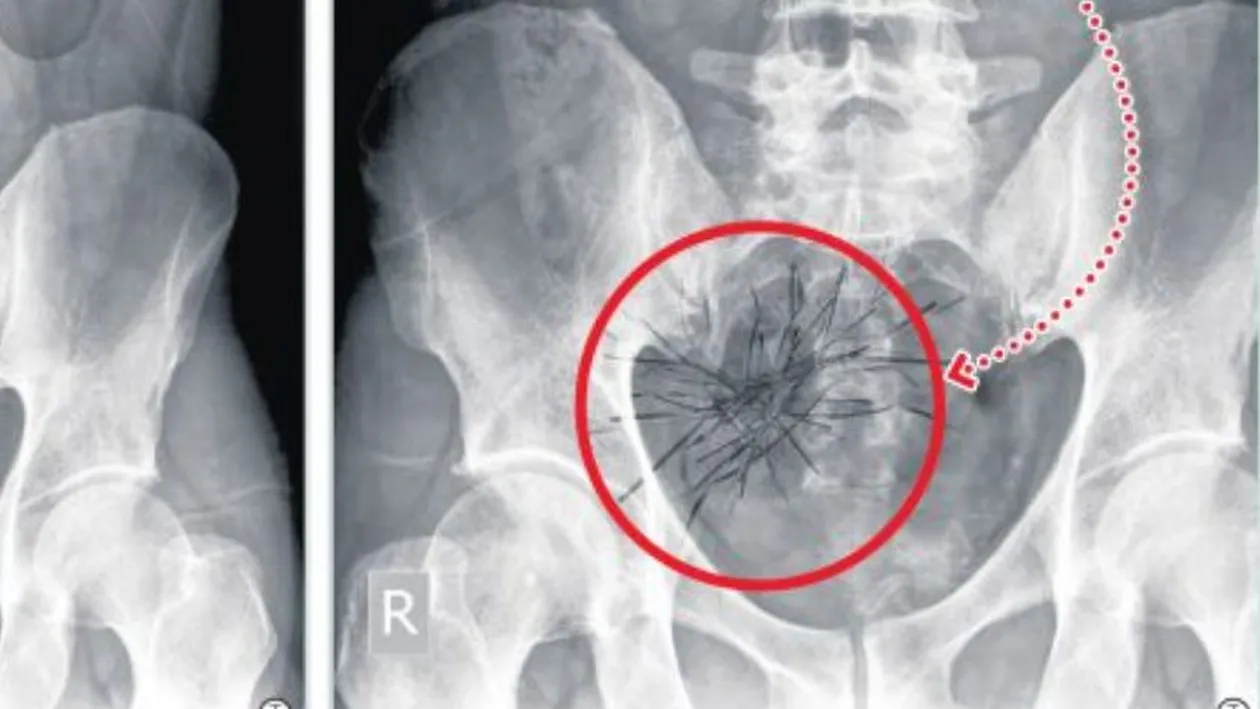

O femeie din Constanţa în vârstă de 61 de ani s-a internat la Spitalul Militar pe data de 18 octombrie 2012. Pacienta a fost operată laparoscopic pentru eliminarea vezicii biliare. După această intervenţie, starea femeii s-a înrăutăţit. Ea a fost supusă unei alte intervenţii chirurgicale , dar starea sa nu s-a îmbunătăţit nici de această dată. Femeia a fost reoperată de urgenţă, dar nici atunci starea pacientei nu s-a îmbunătăţit. Aşa că pe 13 noiembrie a fost supusă unei tomografii computerizate.

O foarfecă se află în zona ficatului, iar cealaltă în zona apendicului. Bolnava cu două foarfece uitate în abdomen a fost operată pentru a treia oară, la trei săptămâni după a doua intervenţie, tot de doctorul Gheorghe Ştefan, pentru îndepărtarea „corpului străin restant intraabdominal”.